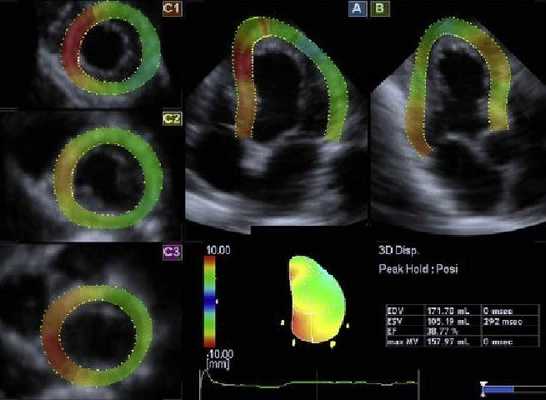

Данный показатель может быть рассчитан по формуле Тейхольца или Симпсона. Расчет осуществляется с помощью программы, автоматически вычисляющей результат в зависимости от конечных систолического и диастолического объема левого желудочка, а также его размеров.

Более удачным считается расчет по методу Симпсона, так как по Тейхольцу в срез исследования при двухмерной Эхо-КГ могут не попасть небольшие участки миокарда с нарушенной локальной сократимостью, в то время как при методе Симпсона в срез окружности попадают более значительные участки миокарда.

Несмотря на то, что на устаревшей аппаратуре применяется метод Тейхольца, современные кабинеты УЗ-диагностики предпочитают оценивать фракцию выброса методом Симпсона. Полученные результаты, кстати, могут отличаться - в зависимости от метода на величины в пределах 10%.